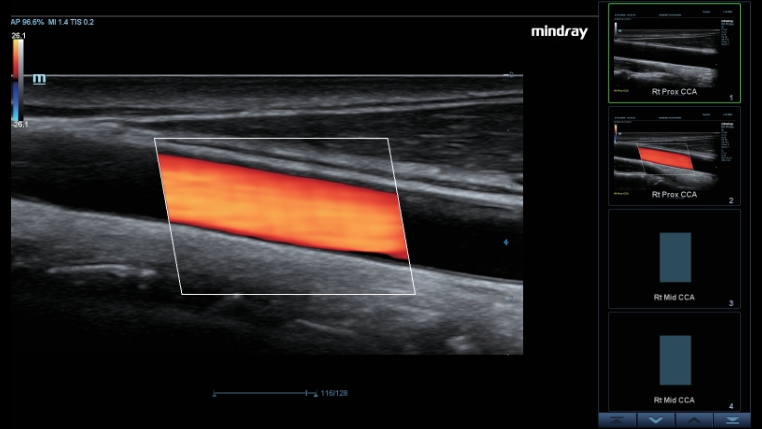

Transduser ComboWave

Dibandingkan dengan transduser tradisional, transduser ComboWave memanfaatkan tipe baru bahan piezoelektrik komposit untuk meningkatkan spektrum akustik dan mengurangi impedansi akustik. Dengan integrasi yang lebih erat dengan teknologi 3T unik dari Mindray, transduser linier ComboWave memungkinkan kinerja luar biasa dengan resolusi gambar yang tinggi dan uniformitas di tiroid, payudara, pembuluh darah, dan lainnya.

Smart Track

Smart Track menyediakan optimasi yang cepat dan cerdas untuk pencitraan vaskular dengan operasi satu sentuhan yang sederhana. Alat ini bisa mengoptimalkan spektrum Warna, Daya, dan PW dengan melakukan pelacakan mandiri dan mengurangi langkah-langkah yang menghabiskan waktu. Oleh karena itu, alur kerja pemeriksaan vaskular disederhanakan dengan tampilan yang optimal.